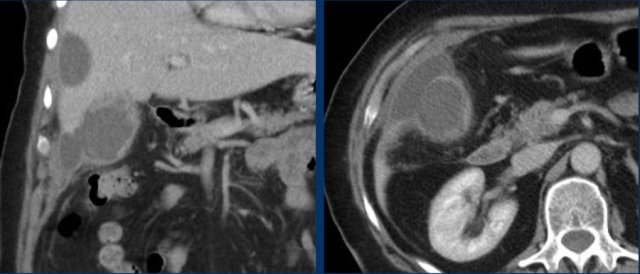

Not infrequently, also on CT scan hydrops of the gallbladder may be identified (fig), but often complementary US is very useful.

Here images of a patient with clinically suspected stomach perforation.

CT shows some stones in a rounded gallbladder.

Complementary US unequivocally demonstrates hydrops (arrowheads).